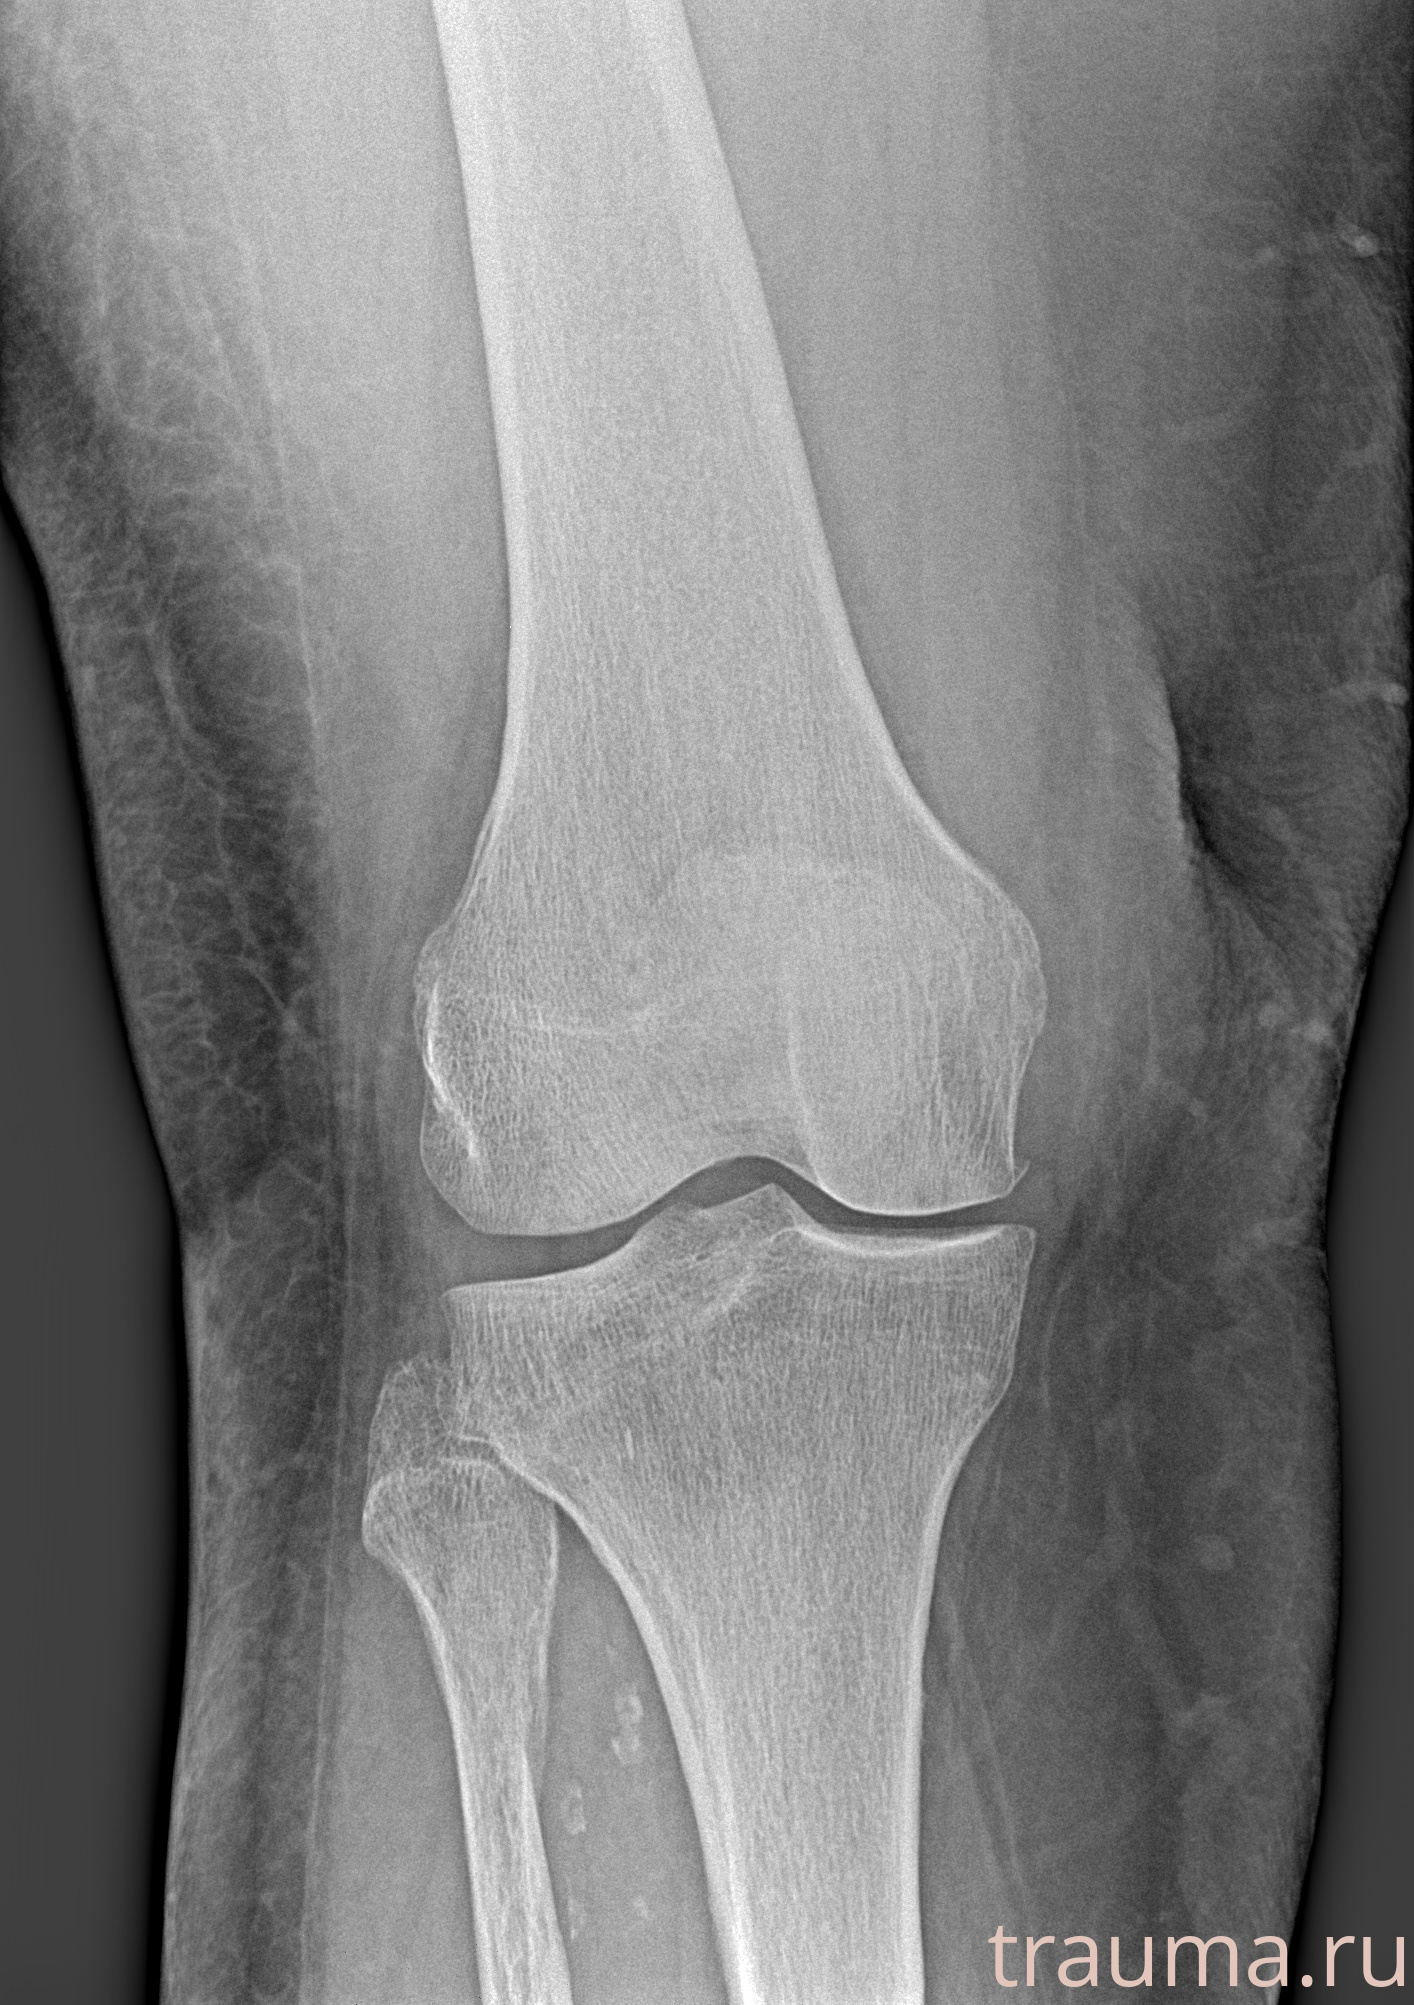

Рентгенограммы

Рентген на дому: по вашему адресу приезжает врач-рентгенолог, травматолог-ортопед с мобильным рентгеновским аппаратом, проводит диагностику травмы или заболевания, делает необходимые рентгенограммы, дает рекомендации по дальнейшему лечению. Получить качественные снимки в домашних условиях возможно благодаря уникальной методике, разработанной МосРентген Центром для института  Склифосовского